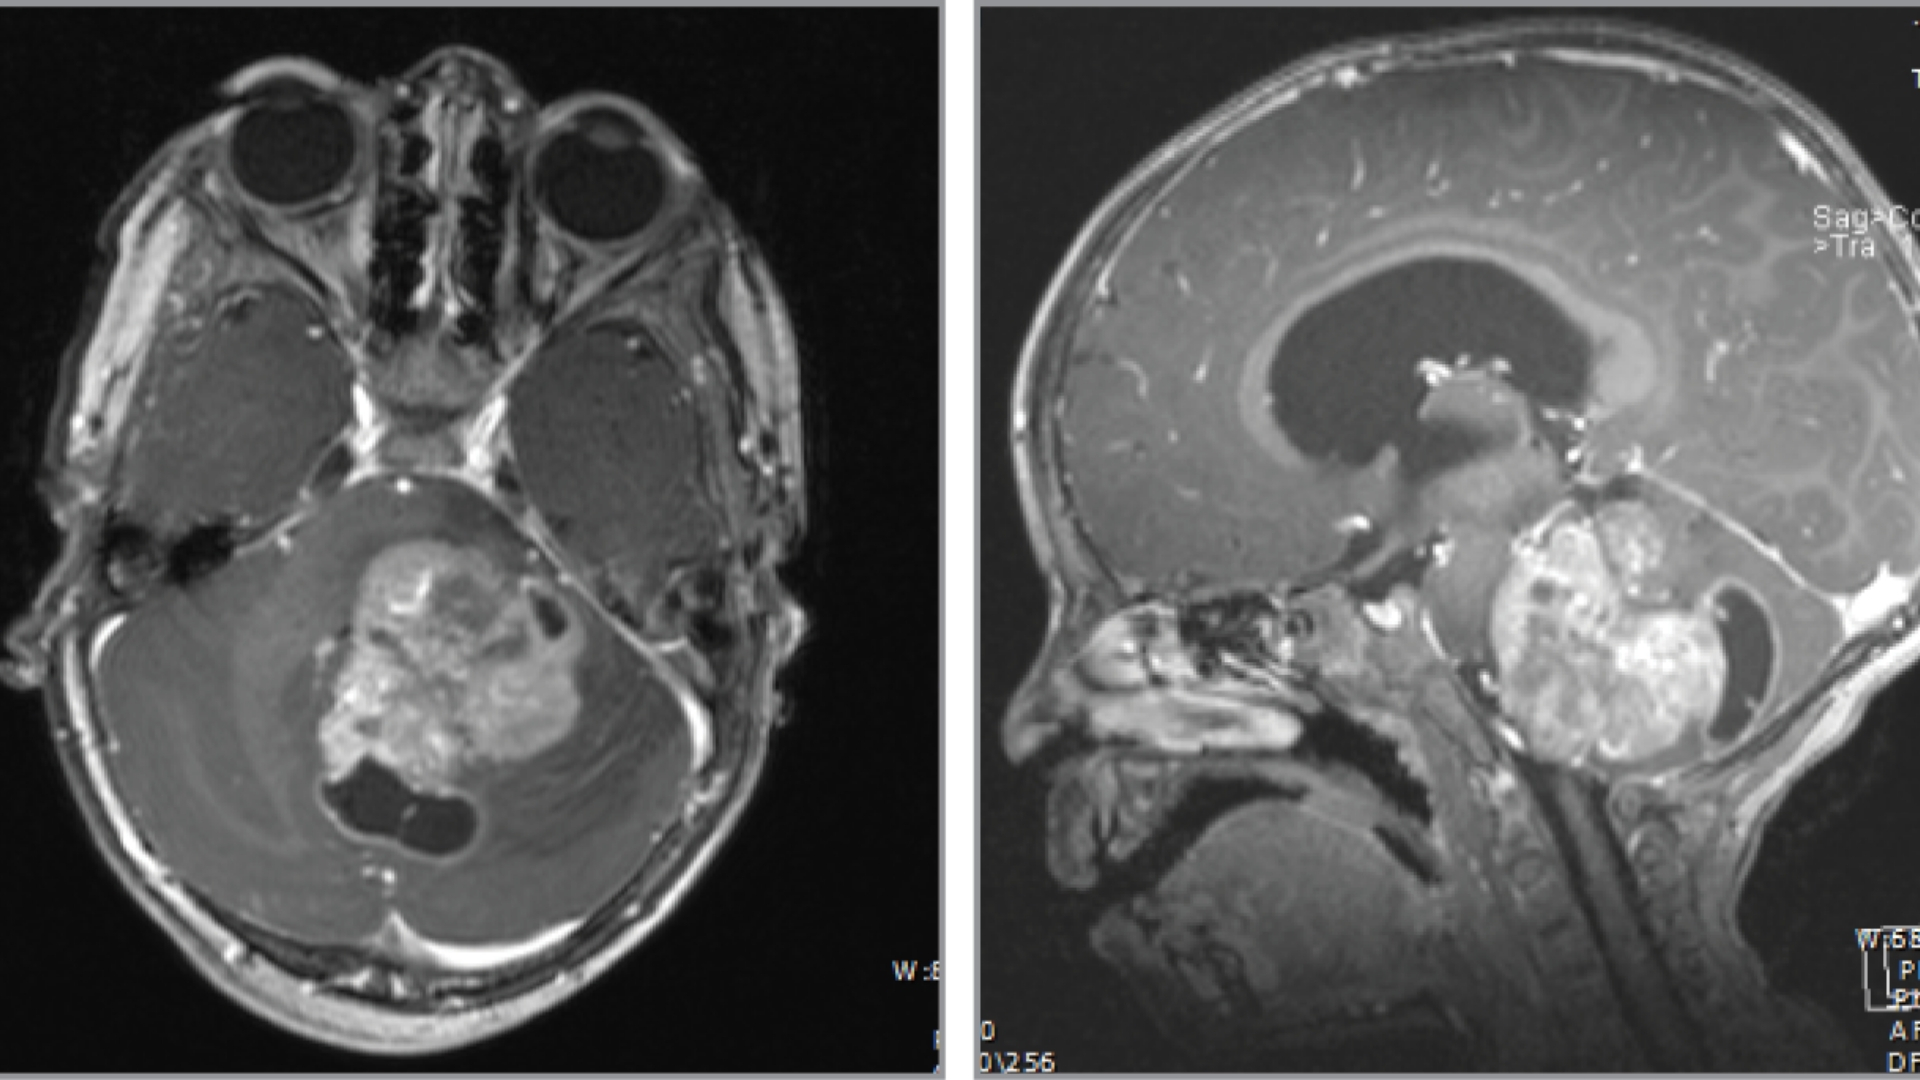

Early-stage DIPG is generally characterized by localized abnormal cell growth confined within the pons, typically detected via MRI imaging. In this early stage, presenting symptoms might be mild, subtle, and easily mistaken for other less-serious conditions.

• Tumor Size: Usually under 2 cm on imaging scans.

• Symptoms: Mild headaches, subtle vision disturbances, slight facial asymmetry.